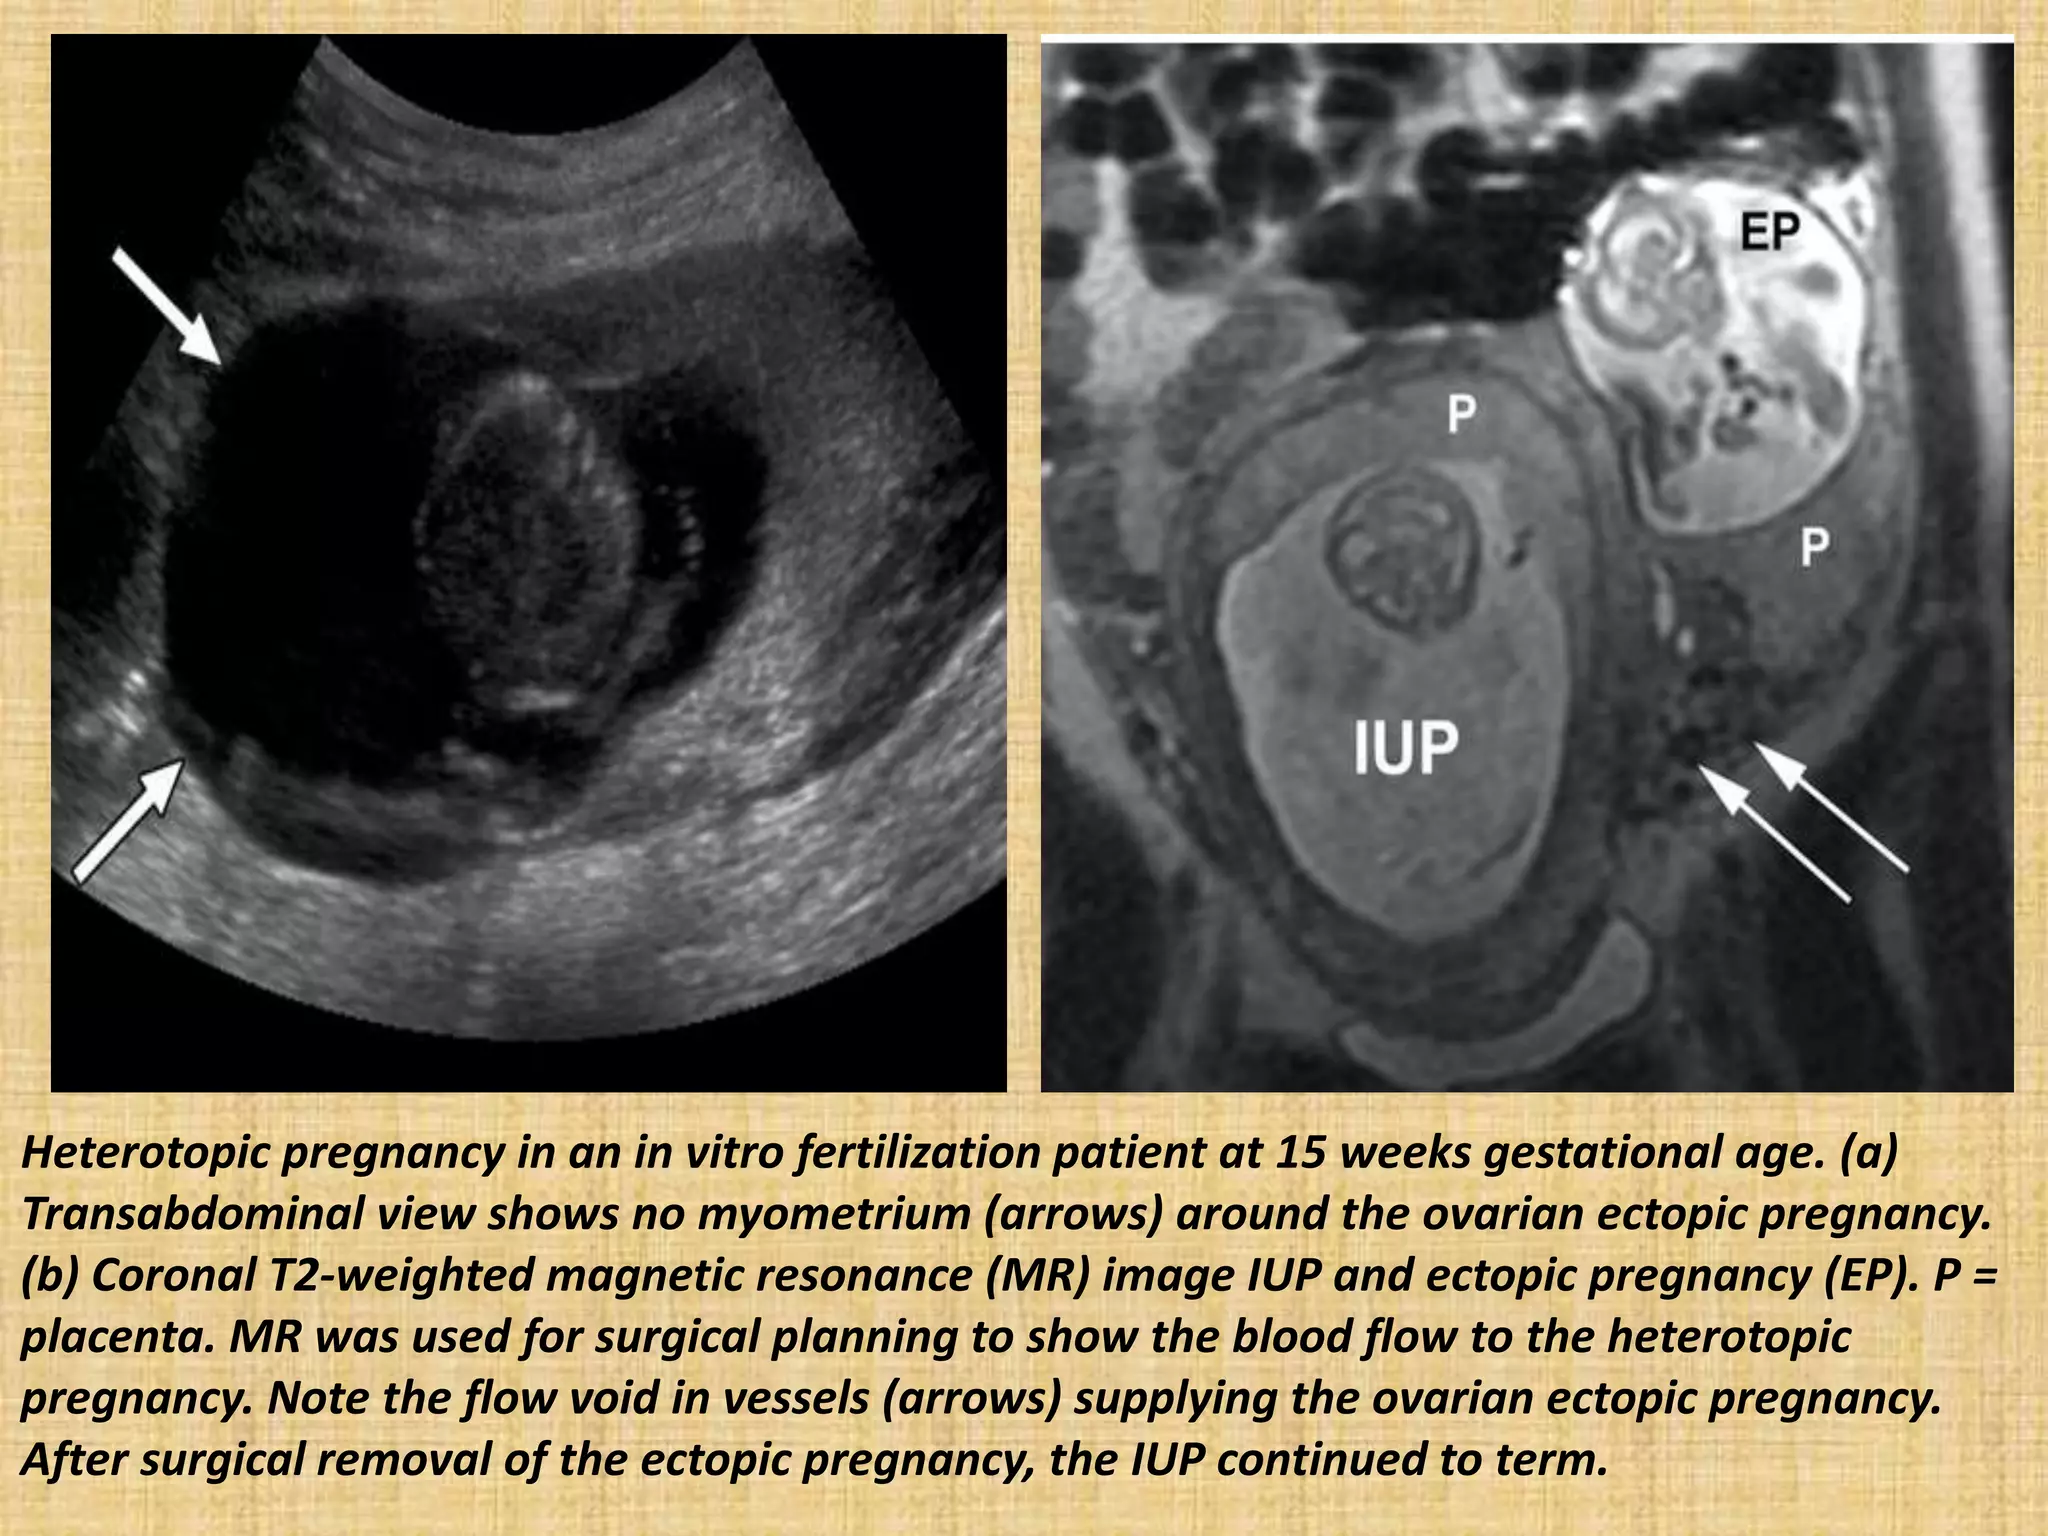

Heterotopic pregnancy in an in vitro fertilization patient at 15 weeks gestational age. (a)

Transabdominal view shows no myometrium (arrows) around the ovarian ectopic pregnancy.

(b) Coronal T2-weighted magnetic resonance (MR) image IUP and ectopic pregnancy (EP). P =

placenta. MR was used for surgical planning to show the blood flow to the heterotopic

pregnancy. Note the flow void in vessels (arrows) supplying the ovarian ectopic pregnancy.

After surgical removal of the ectopic pregnancy, the IUP continued to term.